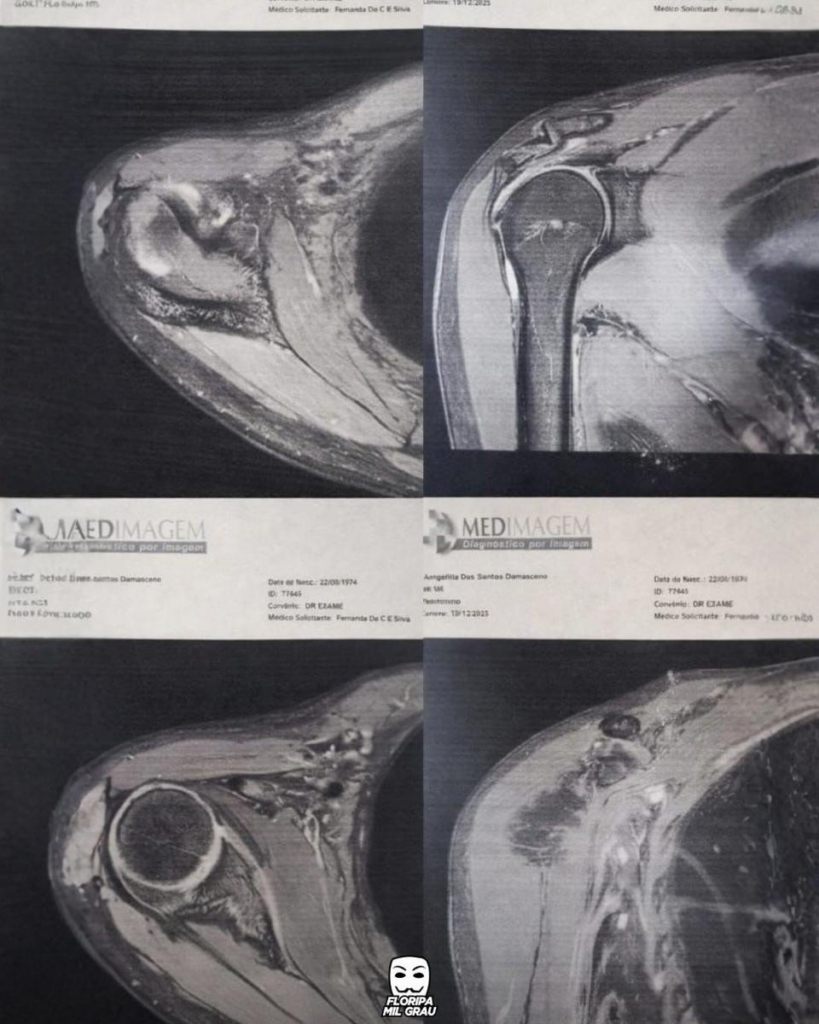

Em dezembro, a família conseguiu pagar uma ressonância do ombro esquerdo, onde a dor era mais intensa.

O exame revelou rompimento total do tendão, além de artropatia degenerativa acromioclavicular, edemas ósseos, tendinopatia com rotura transfixante e retração das fibras, além de bursite.